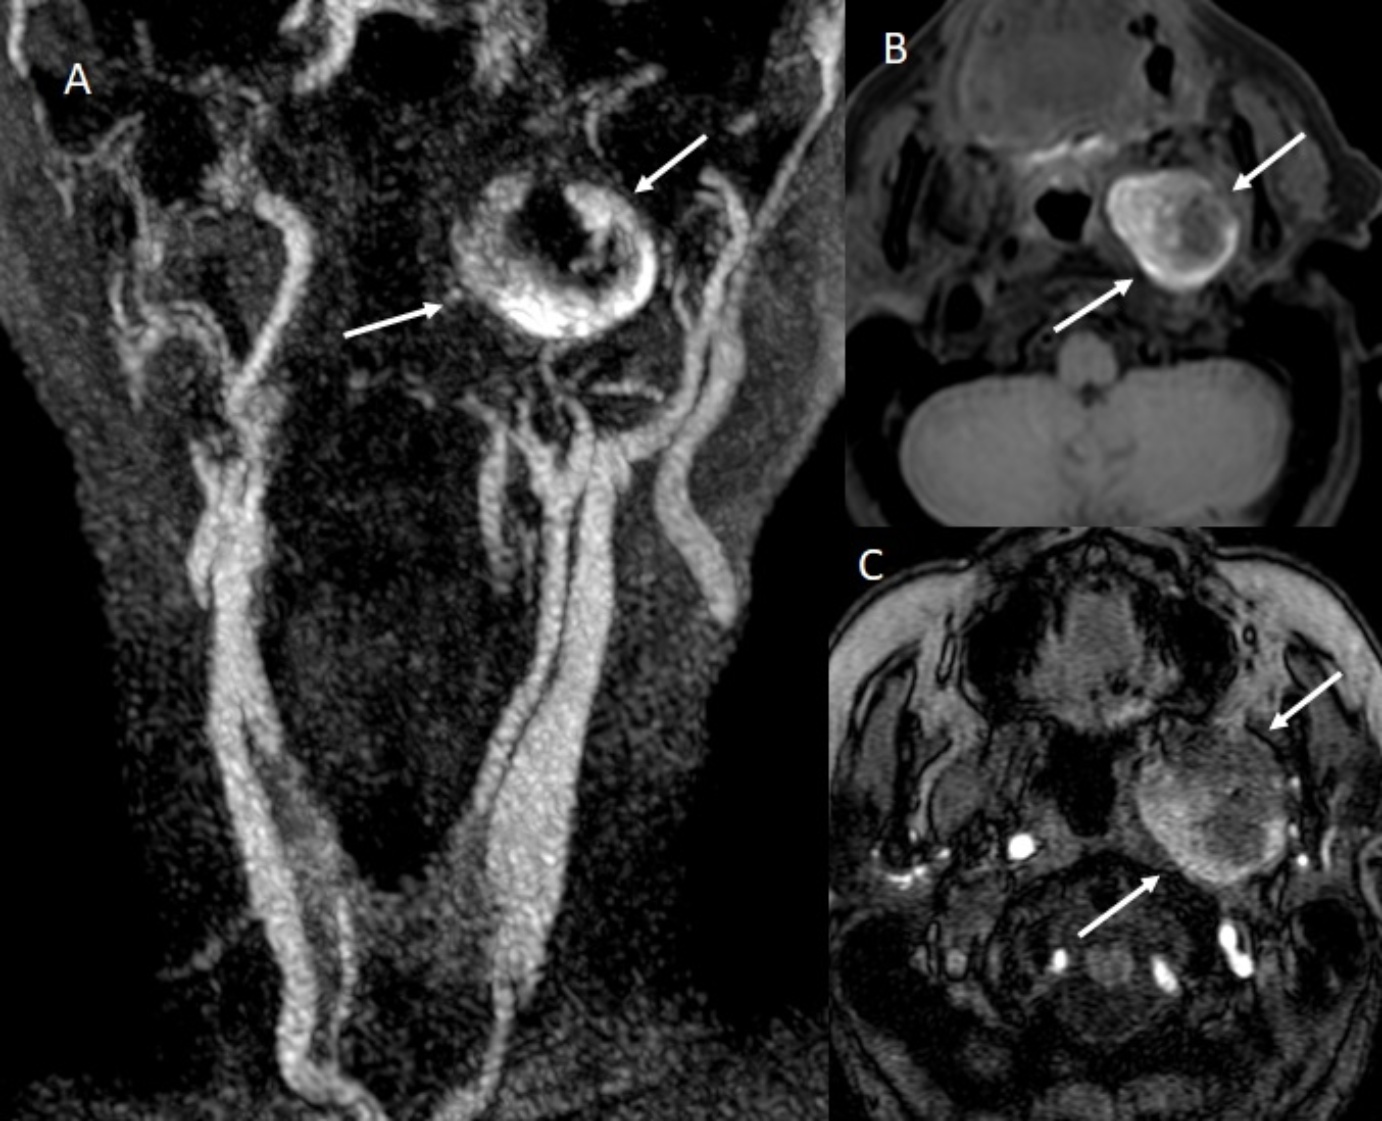

Subsequent Magnetic Resonance Imaging (MRI) of the brain confirmed the presence of ischemic lesions in the left Middle Cerebral Artery (MCA) territory. MR angiography demonstrated a partially thrombosed pseudoaneurysm measuring approximately 1.8 cm in diameter with peripheral enhancement and residual flow at the center (see Figure 1). Digital Subtraction Angiography (DSA) was performed, confirming the diagnosis of a pseudoaneurysm of the distal cervical segment of the left ICA with partial thrombosis and sluggish distal opacification. Imaging also revealed preserved collateral circulation through the circle of Willis, explaining the patient’s maintained perfusion and supporting a conservative approach.

Figure 1. MRI findings. Venous phase of cervical MR angiography (A) demonstrating partial peripheral filling of pseudoaneurysm with contrast material in the distal left internal carotid artery. Axial T1 sequence (B) demonstrating hyperintense thrombus occupying the pseudoaneurysm. 3DTOF MR angiography (C) showing partial internal flow at the lumen of the pseudoaneurysm.